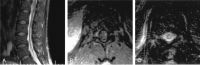

F<sc>ig</sc> 7.

Fig 7.

Patient with intraspinal abnormalities. A, Axial contrast-enhanced T1WI through the region of the cauda equina shows marked abnormal enhancement of the nerve roots, which appear as bright dots in the thecal sac. B, Sagittal gadolinium-enhanced T1WI demonstrates prominently enhancing nerve roots.

F<sc>ig</sc> 8.

Fig 8.

Another patient with intraspinal abnormalities. A, Sagittal T2WI shows abnormal increased signal intensity in the conus medullaris. B, Axial gadolinium-enhanced T1WI shows abnormal foci of enhancement in the conus medullaris. C, Axial T2WI shows markedly increased signal intensity in the thoracic cord. This is appreciated despite image degradation due to artifact.